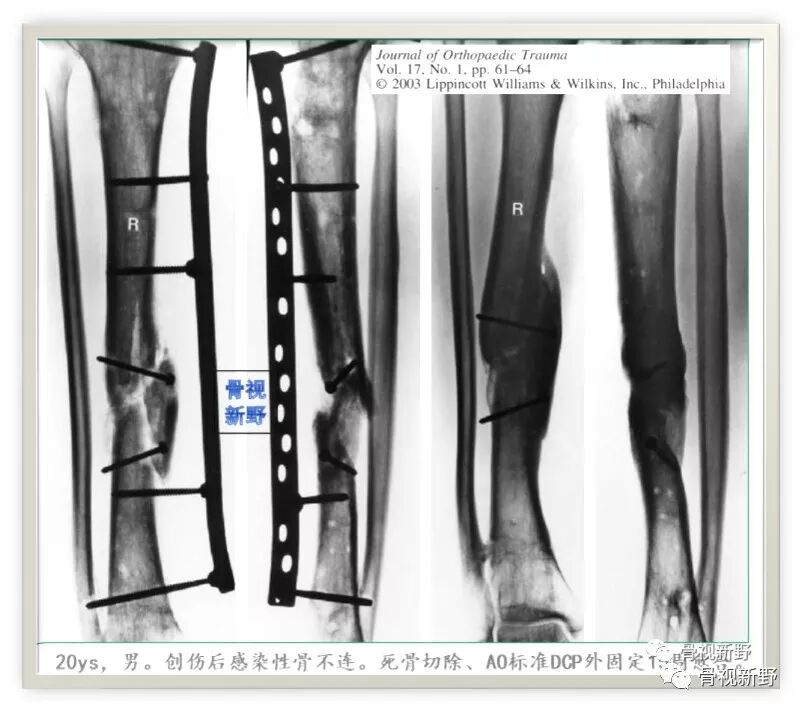

第三次报道:

2003年,Rene K.Marti团队再次报道了将AO标准钢板作为外固定架用于开放性骨折以及骨感染性骨不连的固定病例31例,也取得了较好的疗效。

锁定钢板的外固定应用

Cases